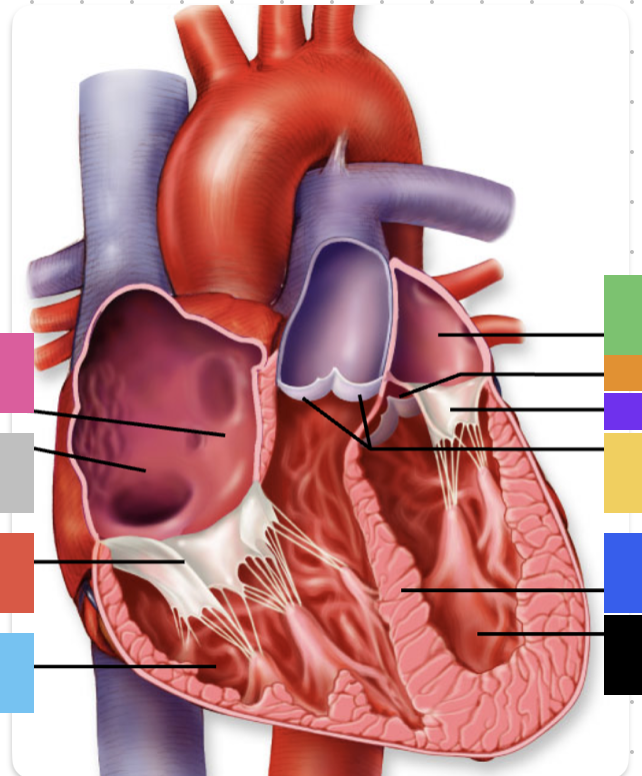

light purple

base

purple

apex

grey

right atrium

pink

right auricle

green

left atrium

green

left auricle

blue

right ventricle

orange

left ventricle

green

coronary (atrioventricular) sulcus

pink

interatrial septum

dark blue

interventricular septum

green

anterior interventricular sulcus

green

posterior interventricular sulcus

orange

aortic valve

yellow

pulmonary valve

red

tricuspid valve (right AV)

purple

bicuspid valve (left AV)

yellow

chordae tendineae

orange

papillary m.

blue

trabeculae carneae - only in ventricles

red

pectinate m. - only in R atrium

pink

fossa ovalis

grey

opening of coronary sinus

green

ligamentum arteriosum

green

fibrous pericardium

blue

parietal pericardium

pink

visceral pericardium (connective tissue) / epicardium (muscle)

purple

myocardium

grey

endocardium

pink

superior vena cava

black arrow

inferior vena cava

black

pulmonary trunk

purple

left pulmonary artery

black

left pulmonary veins

blue

(branches of) right pulmonary artery

yellow

right pulmonary veins

orange

ascending aorta

purple

aortic arch